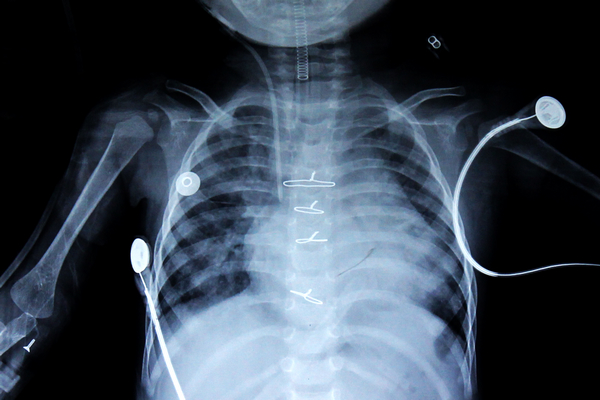

隔日,小鑫怡于下午被推入手术室,经过紧张的几个小时,她的手术顺利完成,安返ICU特护病房。术后第三天,她病情平稳,已经可以拔除气管插管自主呼吸。笔者在小鑫怡术后第四天看到她躺在病床上的样子,显得精神很好,再观察她术后复查的胸片,可看到心脏的大小已经明显小了一圈。小鑫怡出院前三天,即术后第十天时,笔者再去病房探访,她已经从特护病房转到了普通病房,只见小鑫怡的妈妈开心地抱着她坐在床边玩,她水灵灵的眼睛好奇地张望着笔者手中的相机,全然没有病态的模样,令人倍感欣喜。

小鑫怡术后的X光胸片,可以看到心脏小了一圈